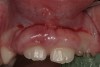

Finally, it must be noted that the psychological and emotional impact of gingival overgrowth receives no or little attention. As increasing numbers of pediatric patients are affected by systemic disease-associated gingival overgrowth, concern should be shown for how pediatric patients interpret what is happening to them and how affected children manage difficulties associated with facial appearance (Figure 1, Figure 2, Figure 3 and Figure 4).

Figure 3  Chronic gingival enlargement of unknown origin in an 8-year-old girl.

Figure 3

Figure 4  Chronic gingival enlargement of unknown origin in an 8-year-old girl. Buccal view.

Figure 4

Facial differences can bring stigma upon children and adolescents, affect their psychosocial development, self-esteem, and quality of life.35 Because of the centrality of the face, the mouth, and a smile in human interactions, the effect of gingival overgrowth on the smiles of thousands of children cannot be minimized. Regrettably, the media and public culture place a huge value on physical appearance, which can result in a lack of opportunity for and acceptance of those who look different.36 Reports of perception of physical appearance and social alienation suggest that children with facial differences undergo serious psychological and emotional problems as a result of the feelings of isolation and powerlessness.37 Because gingival overgrowth is a visible facial feature it can be categorized as a facial difference. Therefore, by extrapolation, the studies cited35-37 support that human relationships and interaction are negatively influenced by the appearance of gingival overgrowth. Life can be only the sum of moments, and moments lost to pain and suffering that are psychological or social in nature can mean as much or more than moments lost to physical pain and suffering.